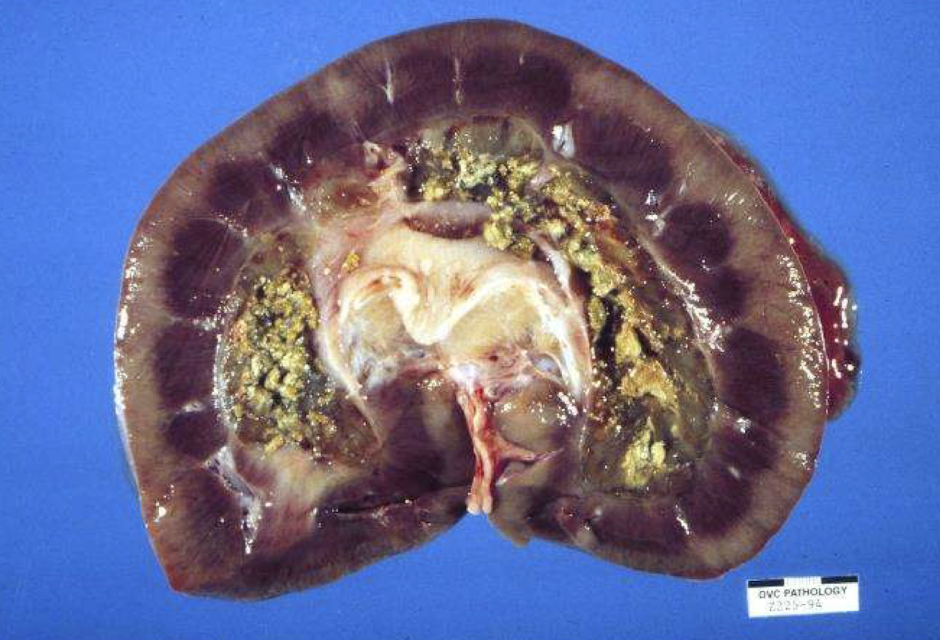

Which urolith types are common vs uncommon in major domestic species?

Cattle:

Common: silica, struvite, carbonate

Uncommon: xanthine

What factors predispose animals to urolith formation?

High levels of calculogenic material in urine

Urine pH (e.g., alkaline → struvite)

Reduced water intake

Infection → change micro environment

Obstruction

Structural abnormalities

Foreign material (suture, bacteria, cells)

Where do urethral obstructions commonly occur in different species?

Ruminants: ischial arch, sigmoid flexure, vermiform appendage in rams

Obstruction severity depends on anatomy and stone characteristics